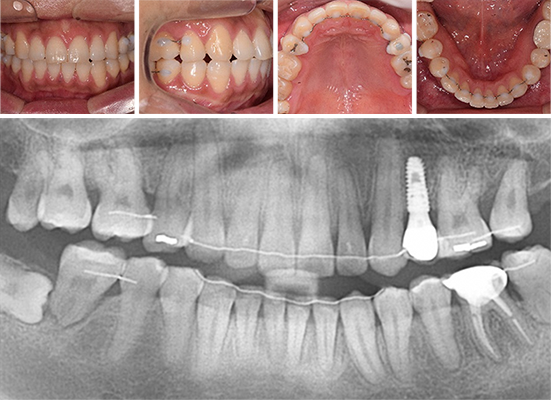

이가 고르지 않고 입술이 나와 보여 개선되기를 원하심. 일반적인 교정치료 방법인 위/아래 작은 어금니 발치 후 앞니 견인을 계획하였으며, 좌측 아래쪽에는 상실된 어금니를 대체하고 있던 임플란트의 뿌리와 지대주 부분만 남아있어 가급적 자연치 보존을 위해 작은 어금니 대신 임플란트를 제거하고 사랑니를 포함한 어금니를 전방으로 당겨오는 치료 진행.

치아 배열이 가지런하게 되었고 제거된 임플란트 공간은 앞니의 후방이동과 어금니들의 전방이동으로 잘 폐쇄되어 본인의 치아를 최대한 보존하며 교정적으로도 만족할 수 있는 결과를 획득하여 유지하고 있습니다.